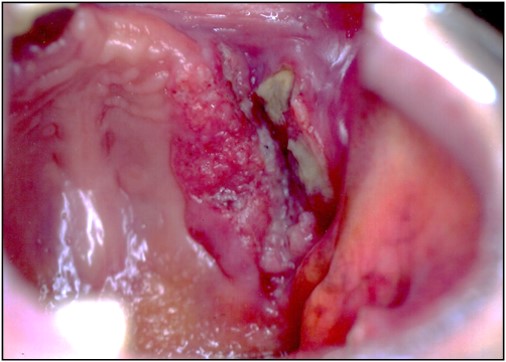

進行がん:歯科、耳鼻科などで大丈夫と言われ痛みが出るまで放置していた症例